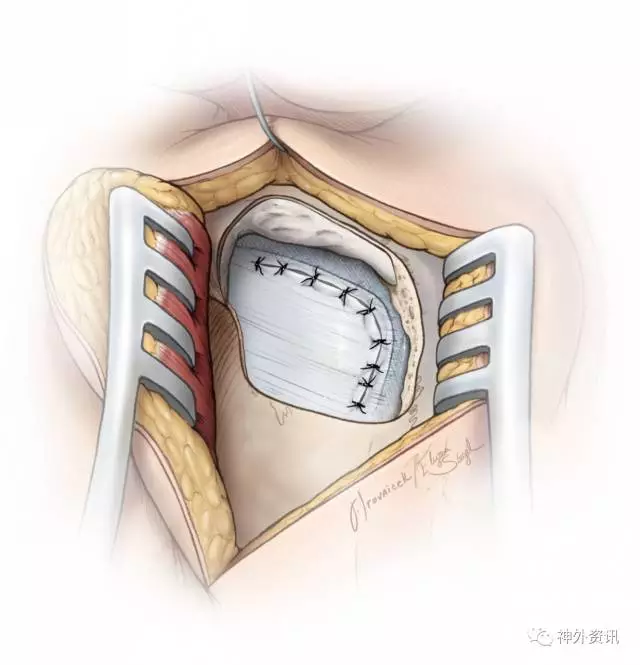

图15. 缝合硬脑膜。

关颅

一般笔者都会追求水密缝合硬脑膜,有时会利用肌肉组织填塞未修复的小缺口。对于微血管减压手术,笔者一般不追求水密缝合硬脑膜,应为这类手术脑脊液切口漏或鼻漏的发生率很低。与肿瘤切除术不同,微血管减压术是非侵袭性手术,术后颅内压增加的风险也较小。

乳突气房需要彻底封闭,笔者通常会用明胶海绵填塞硬膜外腔。放回骨瓣或者用甲基丙烯酸甲酯材料进行修补。最后,逐层关闭肌肉和头皮。